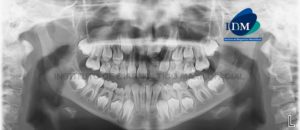

Paciente de 26 años de edad acude al Instituto de Diagnóstico Maxilofacial para evaluación imagenológica de los incisivos superiores. A la evaluación panorámica se evidencio